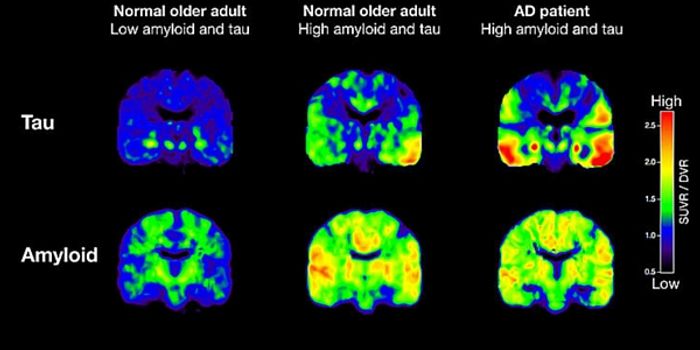

JUN 16, 2016NeuroscienceAlzheimer’s disease (AD) currently affects 5.5 million people in the U.S. over the age of 65, and that number will ...

JUN 08, 2016NeuroscienceIt’s been known for a while that plaques of the protein amyloid beta are part of the pathology of Alzheimer’ ...